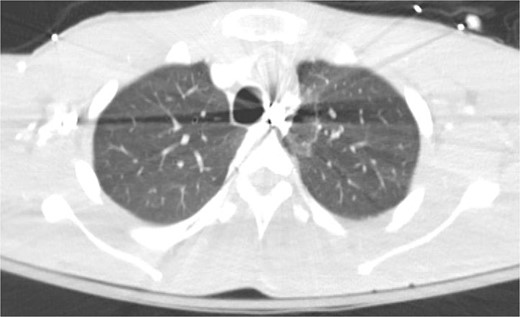

On hospital day (HD) 1, he developed ARDS and required intubation. He became hypotensive, raising concern for mediastinitis, but repeat imaging showed no new findings except that the bullet had migrated below the diaphragm (Fig. 3). Despite his septic appearance, his condition didn’t improve. He was diagnosed with severe AIDS (CD-4 count <100 cells/mm3) and multiple infections (hepatitis A, C, cytomegalovirus, toxoplasmosis, and multi-drug-resistant Pseudomonas pneumonia).